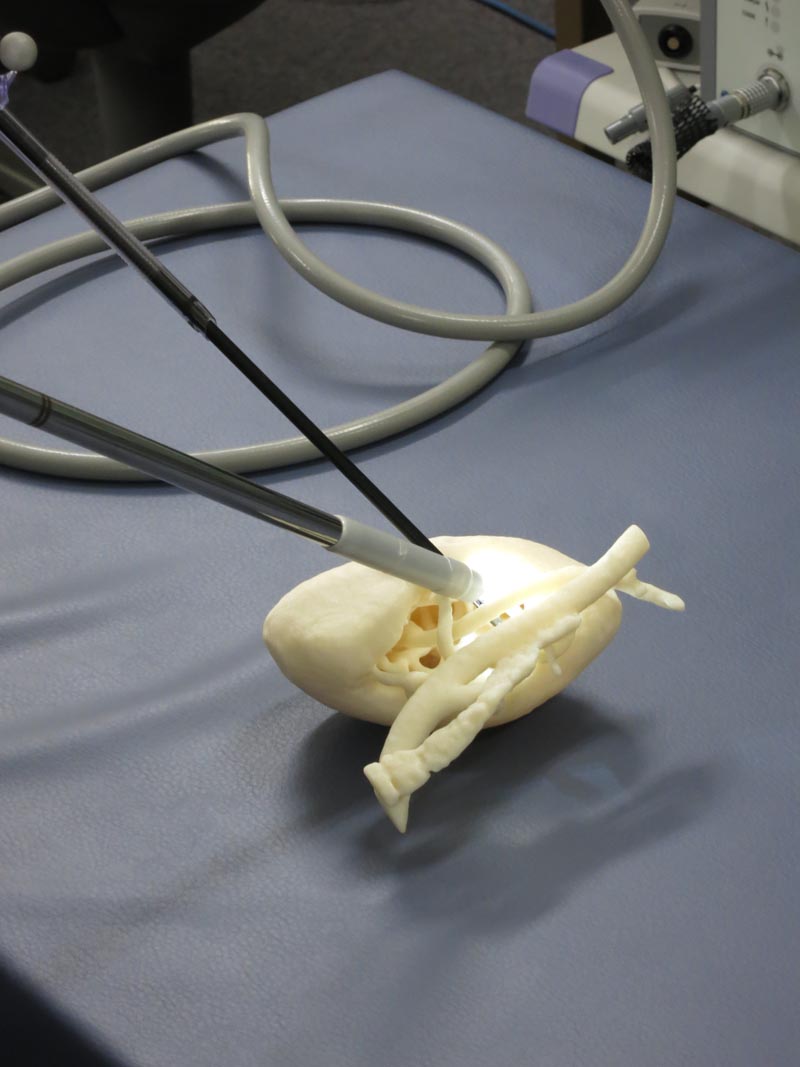

●臓器モデル立体造形

3Dプリンタを利用した臓器モデル立体造形とその利用法に関する研究を行っています。CT画像などの自動解析結果を基に臓器モデル造形に必要なデータを自動生成し、そこから臓器モデルを造形する手法の開発を進めています。手術前のシミュレーション、手術中のナビゲーション、医学・看護教育医療など、新しい利用法についても研究を進めています。

図7 立体造形された臓器モデルを腹腔鏡により観察している様子